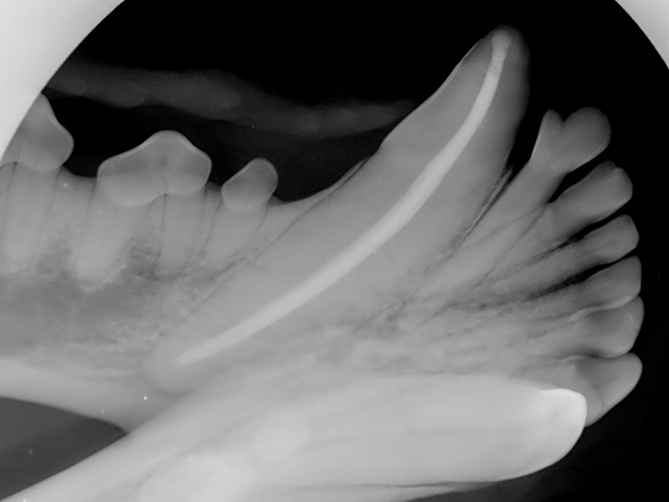

Filling: To prevent future infection, the pulp chamber is filled with an inert material that acts like a plug to keep the inside of the tooth separated from the bone around the tooth root. This material appears white on x-rays.